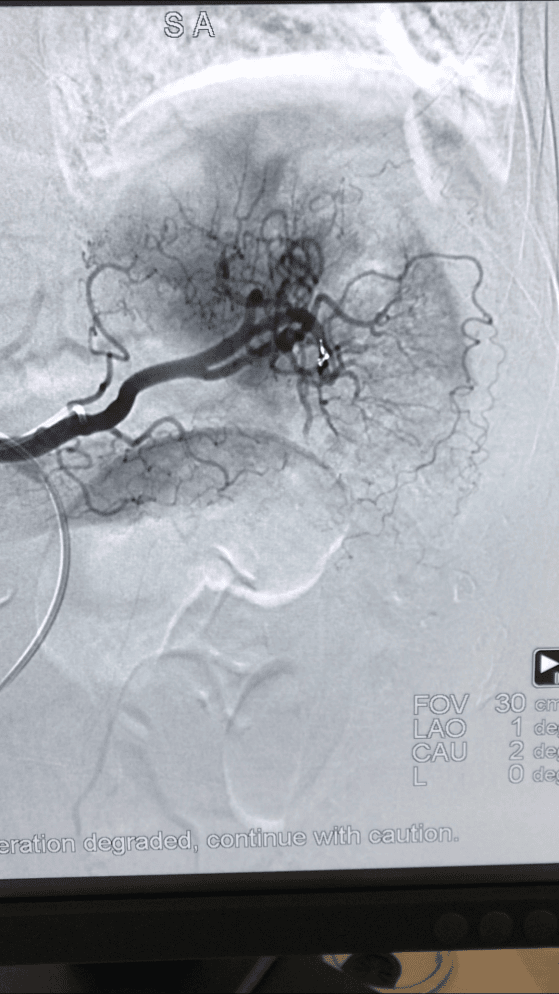

(脾脏破裂出血介入治疗前后造影对比)